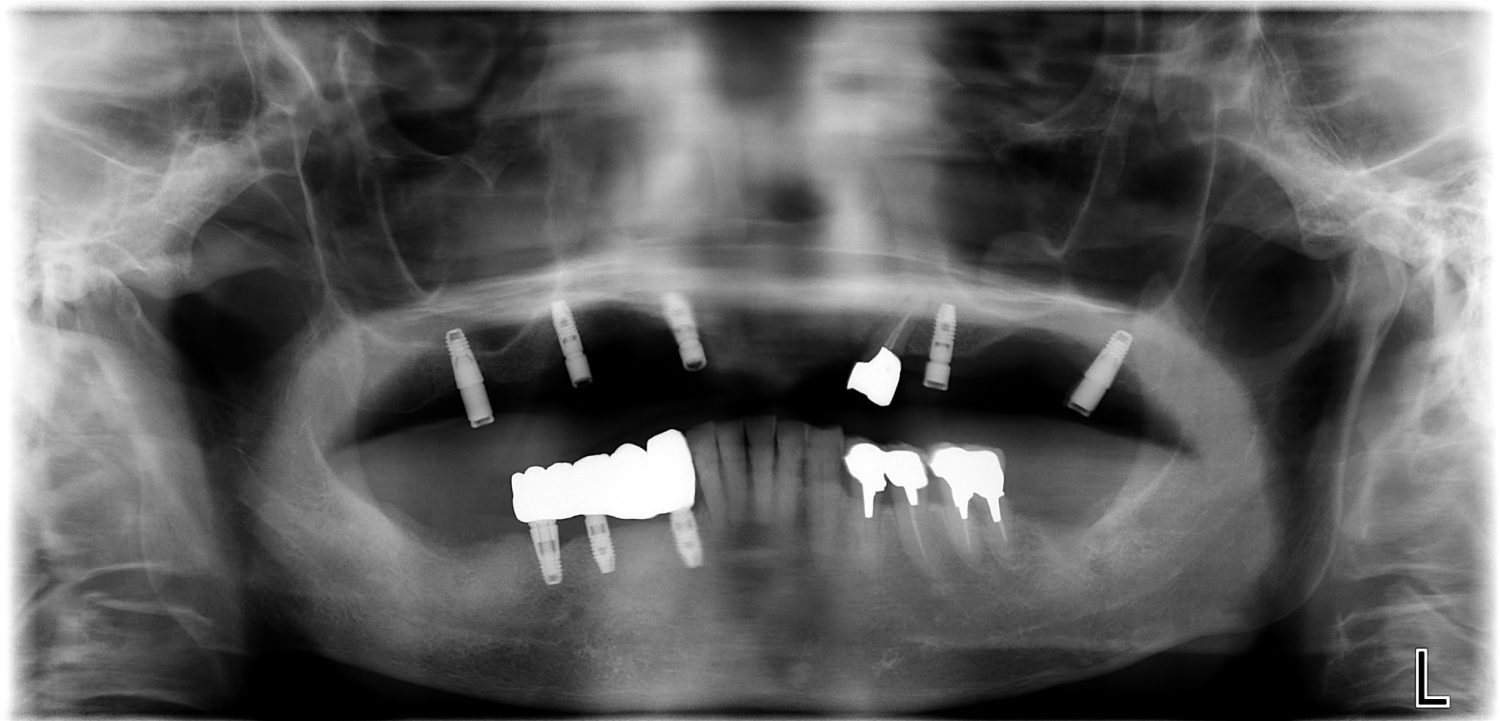

インプラント治療の症例紹介⑤

Before

After

主訴

歯肉腫脹、咬めるようにしたい

治療内容

重度歯周病により全ての残存歯保存不可能な状態。上下顎ボーンアンカードブリッジによる咬合再構成。

治療費

12,621,400円(税込)

治療期間

22ヶ月

通院回数

28回

想定されたリスク

※上部構造の形態が複雑になるため清掃が難しくなる、インプラント周囲炎の恐れがありました。

濱 仁隆先生

浜歯科

上顎8本下顎7本のインプラント体埋入によるボーンアンカードブリッジ。